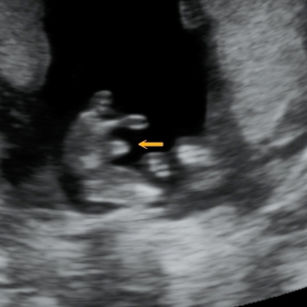

12 Weeks Pregnant

Size: ~2 inches (5 cm), the size of a Lime!

Reflexes developing: baby can open and close fingers.